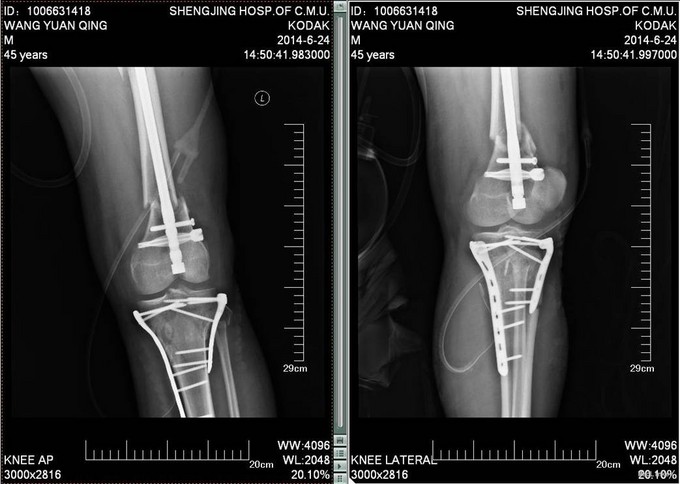

患者自诉于2014-6-1中午骑摩托车被汽车撞翻,伤后昏迷,被肇事司机寄送到当地医院,拍片检查,诊断为:颅脑损伤,脾破裂,左股骨骨折,左胫骨平台骨折。给予保守治疗,并转往盖州市中心医院,急诊下行脾切除术,右下肢给予石膏固定,待患者病情稳定后建议转往上级医院。现患者为求进一步诊治来我院就诊,以“左股骨骨折,左胫骨平台骨折,颅脑损伤,脾切除术后”为主要诊断收入我科。患者伤来无恶心呕吐,腹痛腹胀,胸闷心悸等特殊不适,饮食差、睡眠可,小便可,未大便,体重无明显变化。

诊断:左股骨骨折,左胫骨平台骨折 双侧胸腔积液 脑出血 脾切除术后 患者入院后见患肢肿胀明显,给予患肢抬高位,冷敷,甘露醇消肿等对症治疗,带患肢出现褶皱试验阳性后,全麻下行右股骨干骨折闭合复位髓内针固定术;左胫骨平台骨折切口复位钢板内固定术,术后患者肿胀明显,给予抗炎,消肿,冷敷,患肢抬高等对症治疗。患者每天换药观察切口愈合情况,无红肿及渗出,待伤口14天后予以拆线治疗,予以出院,给予康复处方。